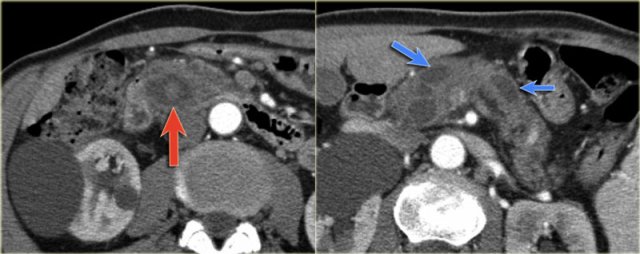

Scroll through the images of a large main duct and branch-duct IPMN.

There is obstruction of the common bile duct with dilatation of the intrahepatic bile ducts (blue arrows).

Notice the extremely widened main pancreatic duct (red arrow).

CT-images of an IPMN with a dilated pancreatic duct (blue arrows).

Notice enhancing solid nodule in the pancreatic head (red arrow).